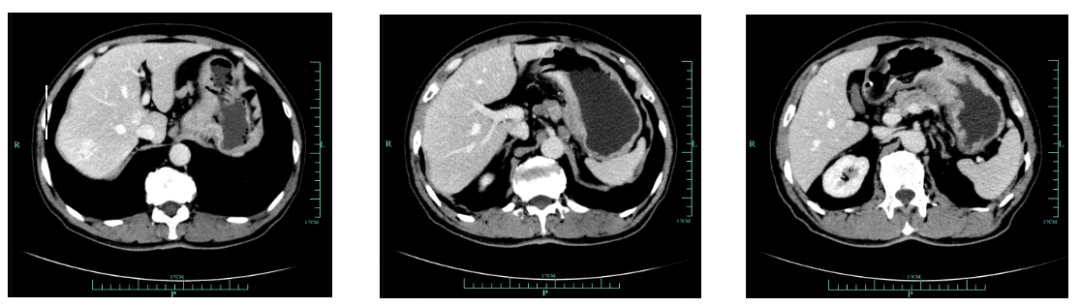

一线化疗疗效评估(2019.6 vs 2019.4):胃癌术后改变。影像评估CR。

影像学评估:胃癌术后改变。持续CR。